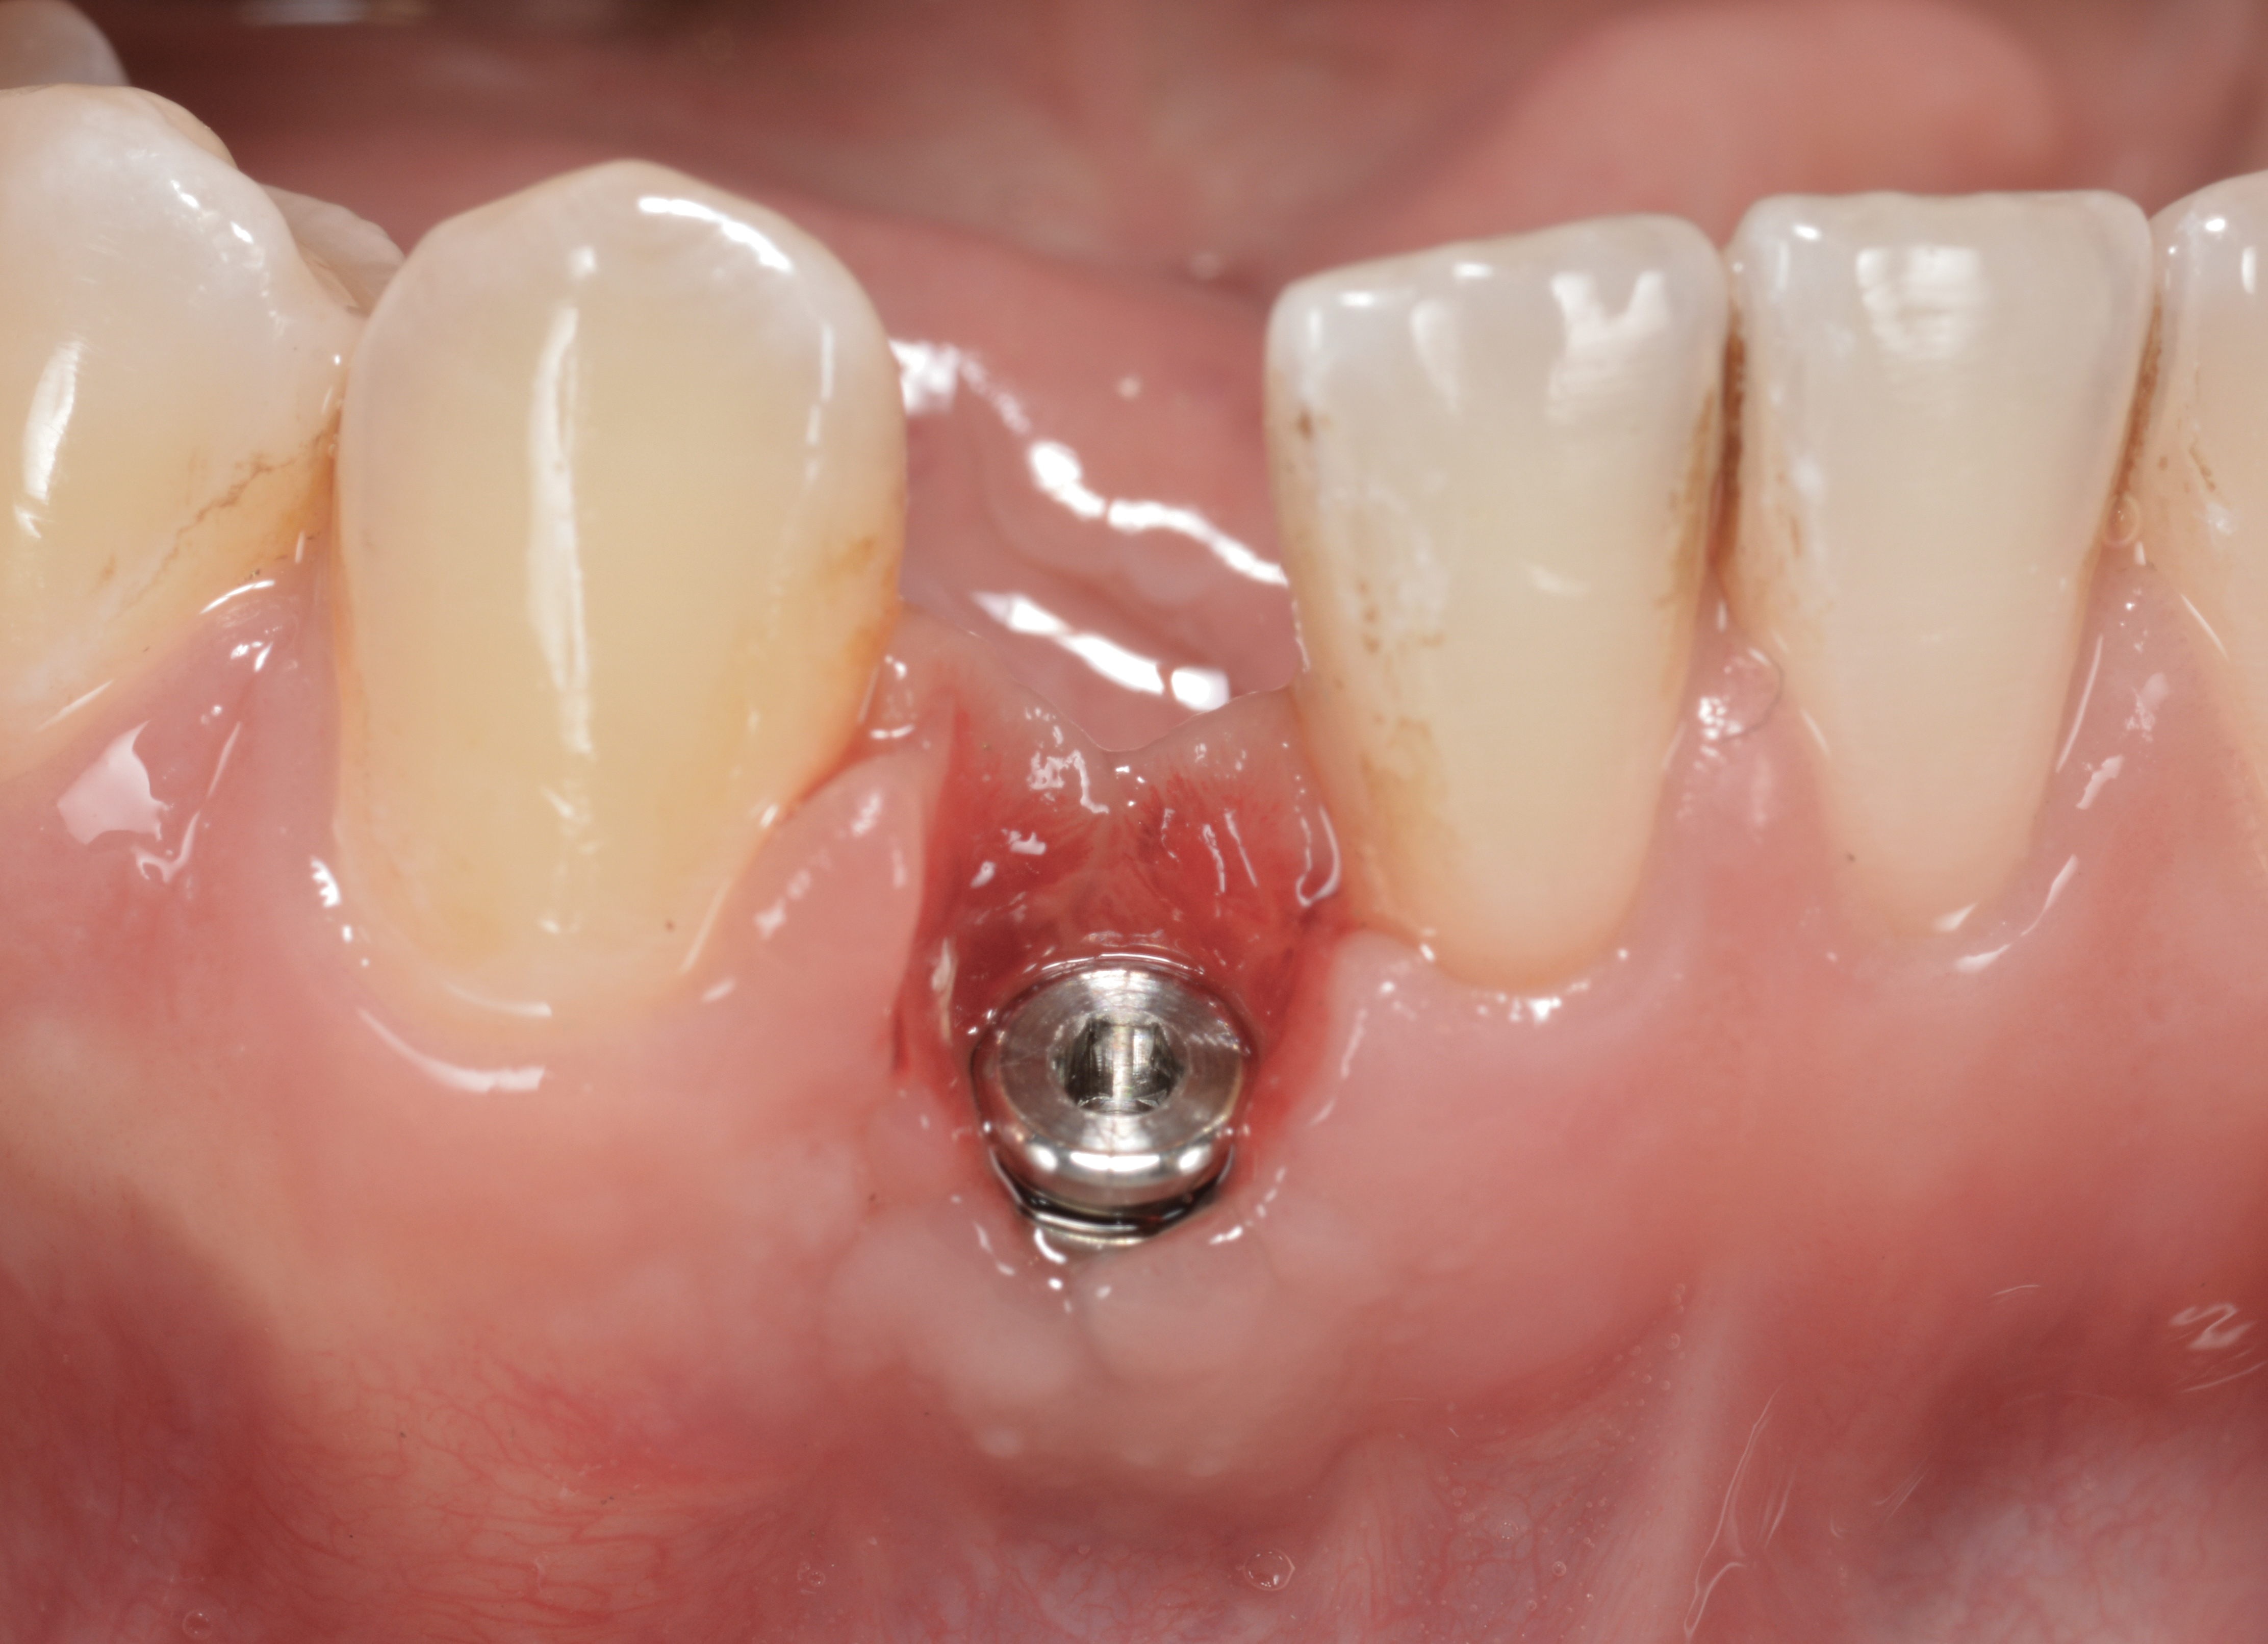

Fig 15. The implant-supported restoration of tooth No. 19 presented with a lack of attached keratinized gingiva, shallow buccal vestibule, and 2 mm of buccal recession.

Figure 15

Fig 16. The restoration exhibited an 8-mm pocket upon probing, with bleeding on the buccal aspect.

Figure 16